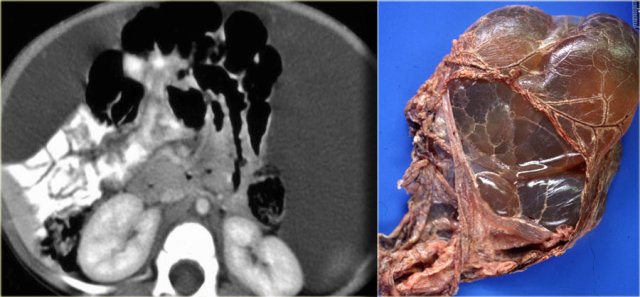

The case on the left is also a lymphangioma.

Notice that CT does not always appreciate the septations, although the specimen clearly shows multiple septations.

Ultrasound or MR depict these septations better than CT.